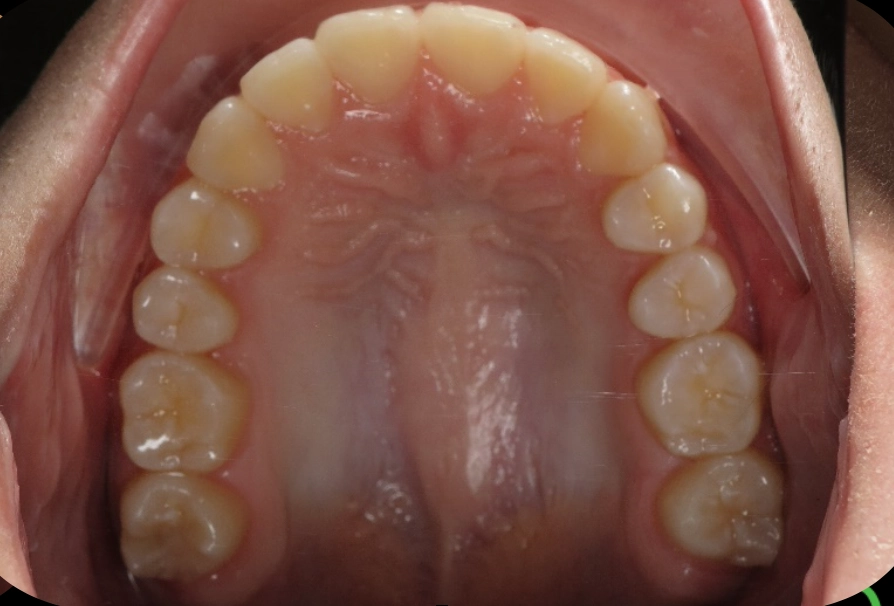

Patient treated with EXPANSION and braces

Before

After